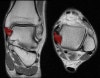

2. Calcaneofibular ligament

Coronal (left) and axial (right) T1W images assessing the normal calcaneofibular ligament.